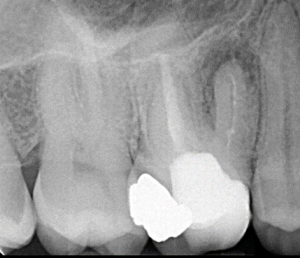

Clinical Cases